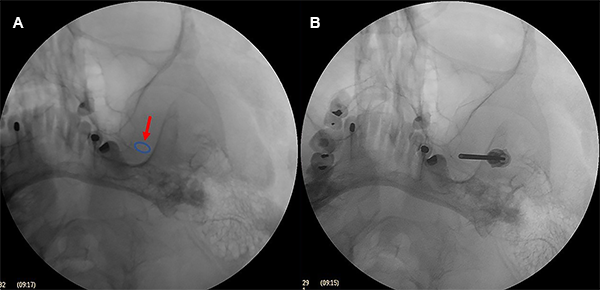

La aguja guiada de los tres puntos referenciales en la hemicara y bajo control fluoroscópico debe dirigirse a un punto en la línea clival 5-10 mm por debajo del piso de la silla turca o en la intersección del peñasco del hueso temporal con el clivus, hasta que se engancha en el agujero oval. Es innecesario penetrar más allá del agujero. La aguja simplemente permanece en el agujero oval (Figura 5).

Cuando es difícil ingresar al foramen oval se puede obtener una imagen en fluoroscopia en incidencia submento-vertical para visualizar el foramen oval; sin embargo, como esta incidencia es difícil de realizar en una cama quirúrgica, se realizó una incidencia fronto-submaxilar oblicua (Figura 6).

Figura 6: Incidencia fronto-submaxilar. El agujero oval izquierdo se ve medial a la rama de la mandíbula y lateral al maxilar sobre el borde del peñasco.

Se retiró el mandril y se introdujo un punzón guía de punta redonda de 13 cm de longitud que atravesó el foramen oval y se hizo el control radiográfico, el punzón facilita la entrada del catéter Fogarty a través del cavum de Meckel. Si hay una resistencia al avance del punzón guía, entonces la aguja no está en la posición correcta.

Se retiró el punzón y se introdujo un catéter Fogarty 4F a través de la luz de la aguja y la punta del catéter debe atravesar 18 mm desde el foramen oval hasta el poro trigeminal.

El balón con una jeringa de insulina previamente cargada con contraste radiológico (Iopamidol 612,4 mg /ml) fue lentamente insuflado usualmente entre 0.5 a 1 ml hasta obtener un balón en forma de pera (Figura 7A), o en reloj de arena en tamaño completo (Figura 7B). Se mantuvo insuflado por 60 segundos.

Figura 7: Formas de balón. (A) Pera, (B) Reloj de arena, (C) Oval.